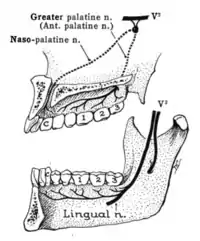

Sensory branches

The ophthalmic, maxillary and mandibular branches leave the skull through three separate foramina: the superior orbital fissure, the foramen rotundum and the foramen ovale, respectively. The ophthalmic nerve (V1) carries sensory information from the scalp and forehead, the upper eyelid, the conjunctiva and cornea of the eye, the nose (including the tip of the nose, except alae nasi), the nasal mucosa, the frontal sinuses and parts of the meninges (the dura and blood vessels). The maxillary nerve (V2) carries sensory information from the lower eyelid and cheek, the nares and upper lip, the upper teeth and gums, the nasal mucosa, the palate and roof of the pharynx, the maxillary, ethmoid and sphenoid sinuses and parts of the meninges. The mandibular nerve (V3) carries sensory information from the lower lip, the lower teeth and gums, the chin and jaw (except the angle of the jaw, which is supplied by C2-C3), parts of the external ear and parts of the meninges. The mandibular nerve carries touch-position and pain-temperature sensations from the mouth. Although it does not carry taste sensation (the chorda tympani is responsible for taste), one of its branches—the lingual nerve—carries sensation from the tongue.

Dermatomes

The areas of cutaneous distribution (dermatomes) of the three sensory branches of the trigeminal nerve have sharp borders with relatively little overlap (unlike dermatomes in the rest of the body, which have considerable overlap). The injection of a local anesthetic, such as lidocaine, results in the complete loss of sensation from well-defined areas of the face and mouth. For example, teeth on one side of the jaw can be numbed by injecting the mandibular nerve. Occasionally, injury or disease processes may affect two (or all three) branches of the trigeminal nerve; in these cases, the involved branches may be termed:

Diagram of facial sensory nerves (front view)

Diagram of facial sensory nerves (front view) Trigeminal nerve in yellow